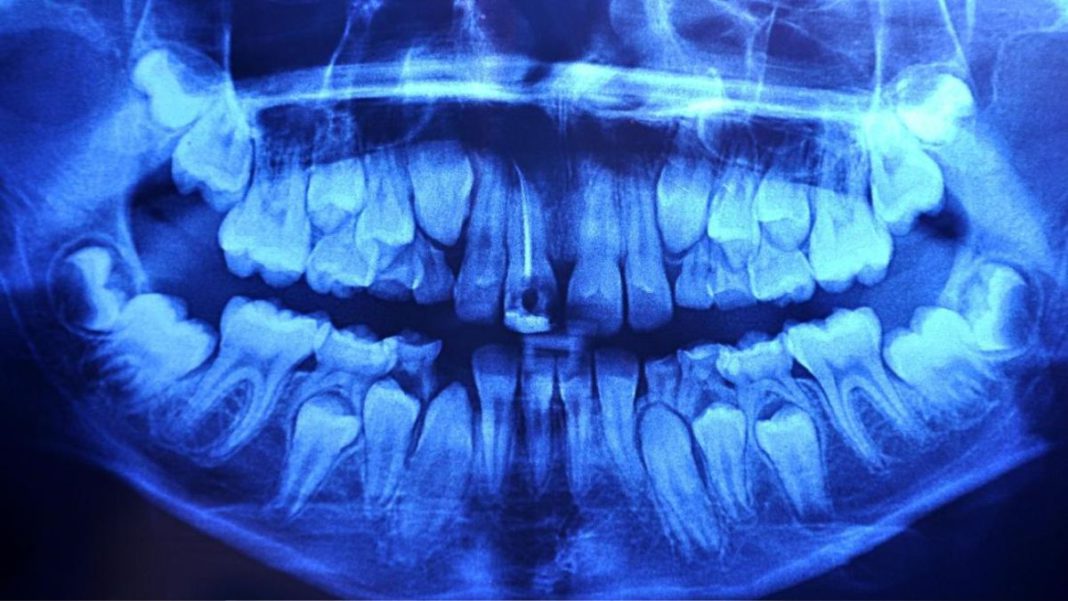

Cephalometric Xrays Santa Clarita, California Kidz Dental Care SCV

from kidzdentalcare.com